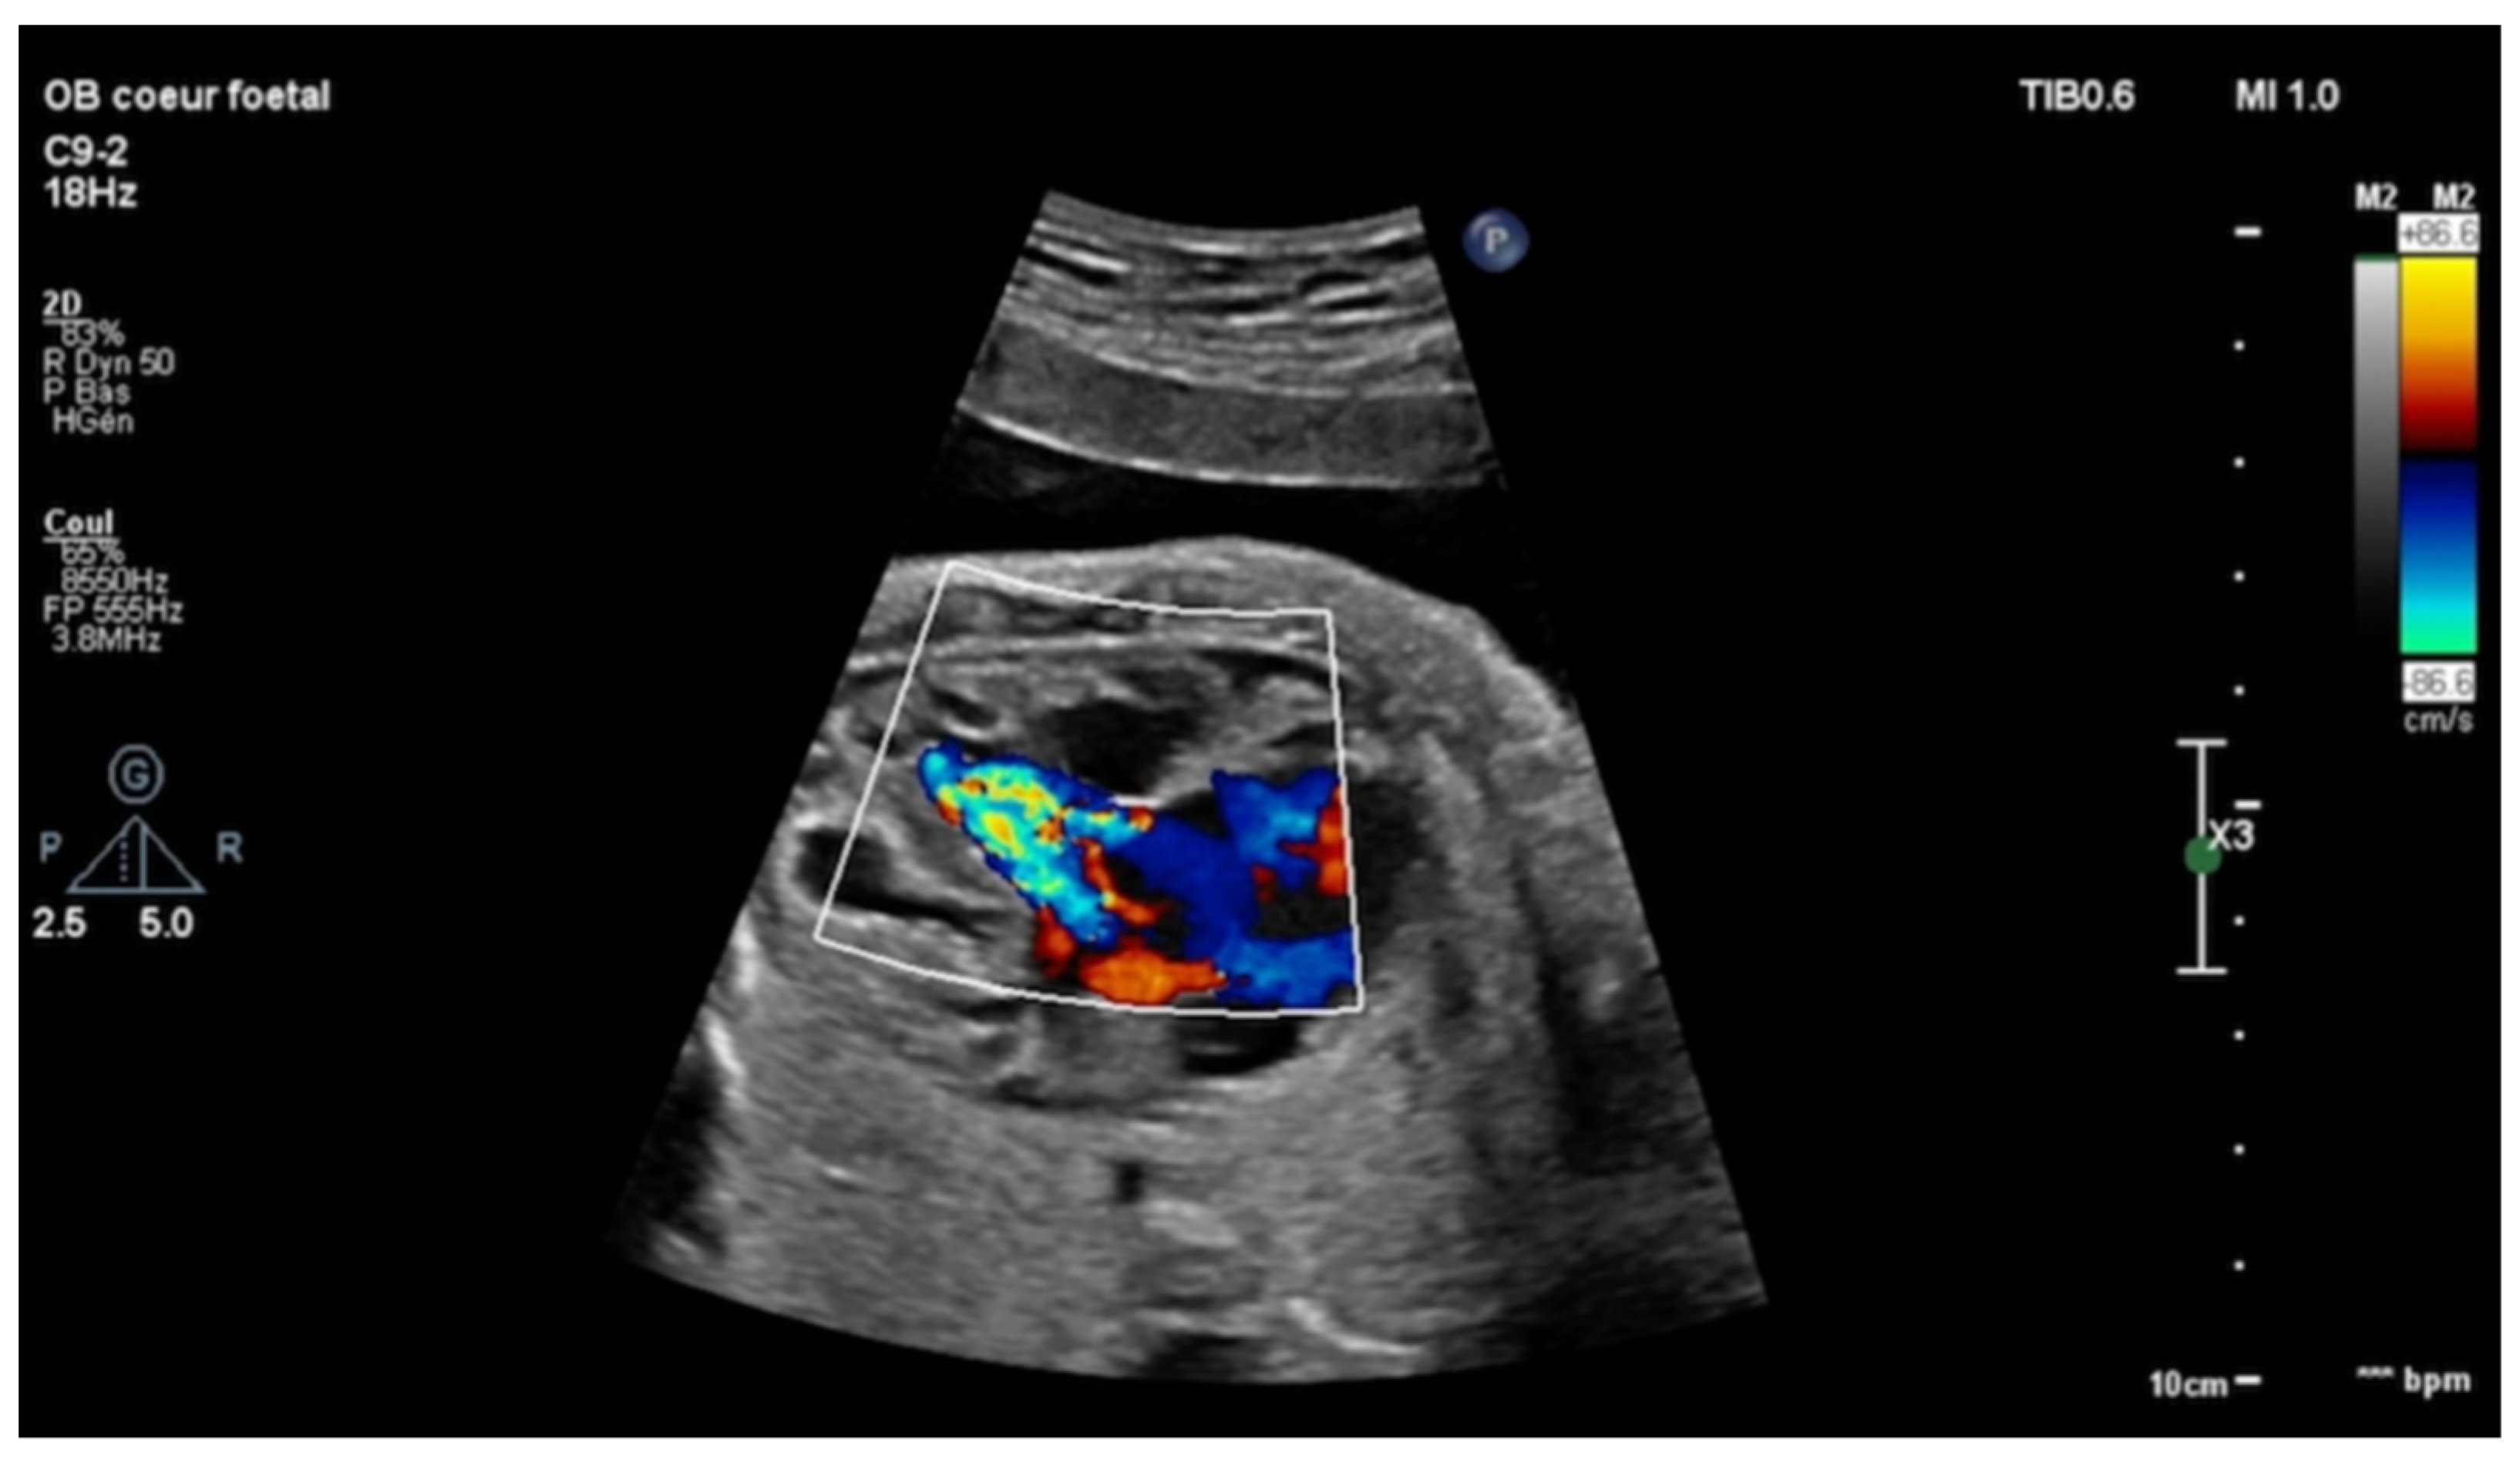

Echocardiography in a fetus at 25 weeks of gestation (WG) from a 19-year-old woman, without history of familial CHD, showed: (i) a typical partial common AVCD with a cleft on the left atrioventricular valve (AVV) without stenosis or leak and a large ostium primum atrial septal defect (ASD); (ii) Ebstein abnormality of the right AVV with a significant leak, causing a dilatation of the right atrium (RA) (Figure 1; Videos S1 and S2); (iii) “functional pulmonary atresia” with inconstant anterograde passage and (iv) retrograde flow in a tortuous ductus arteriosus. Other cardiac structures were normal. Cytogenetic analysis via amniocentesis had normal results. At 30 WG, moderate atrialization of the right ventricle and a pulmonary insufficiency were noted (Figure 2).

Figure 2. Short-axis view: color Doppler: retrograde flow in the pulmonary artery with pulmonary insufficiency.